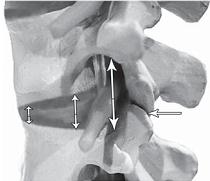

МРТ № 3

На МРТ № 3 — поясничный отдел позвоночника. (На данном «контрольном» снимке наблюдаются остаточные явления дегенеративно-дистрофического процесса в сегменте LV-SI после устранения методом вертеброревитологии секвестрированной грыжи межпозвонкового диска.)

В поясничном отделе форма позвоночного канала, создаваемая телом и дужками позвонка, вариабельна, но чаще она пятиугольная. В норме позвоночный канал в пояснично-крестцовом отделе сужен в переднезаднем диаметре на уровне LIII и LIV позвонков. Его диаметр каудально увеличивается, и поперечное сечение канала приобретает форму, близкую к треугольной, на уровне LV-SI. У женщин канал имеет тенденцию к расширению в нижней части крестцовой области. Сагиттальный диаметр значительно уменьшается от LI к LIII почти неизменен от LIII к LIV и увеличивается от LIV к LV. В норме переднезадний диаметр позвоночного канала в среднем равен 21 мм (15–25 мм).

Существует простая и удобная формула определения ширины позвоночного канала:

нормальный сагиттальный размер не менее 15 мм;

11–15 мм — относительный стеноз;

менее 10 мм — абсолютный стеноз. Уменьшение этого соотношения свидетельствует о сужении канала.

Высота поясничных межпозвонковых дисков 8–12 мм, нарастает от LI до LIV-LV, обычно уменьшается на уровне LV-SI